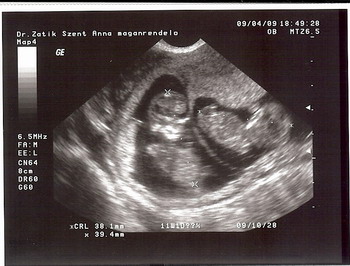

Én is voltam ma uh-n, szépen nőnek a csajok, 1900g-osak, és végre Mira is befordult fejjel lefelé. De annyit feszegetik magukat! Néha csillagokat látok.